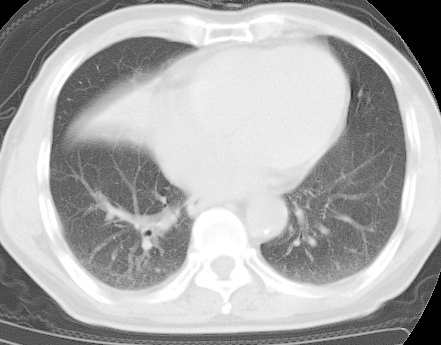

标题: CT24032:男65岁,咳嗽,吸烟20余年,无发热,咳痰 [打印本页]

标题: CT24032:男65岁,咳嗽,吸烟20余年,无发热,咳痰

考虑右肺中叶不张,请大家发表意见

右肺中叶不张、肺门轮廓增大,占位不除外;建议增强,必要时支气管镜详查。

右肺中叶支气管闭塞,中叶肺不张,右侧肺门见肿块影。中心型肺癌的可能大。建议支气管镜检查。

右中叶体积明显缩小,且其支气管未显示,先考虑:中心型肺癌班右中叶肺不张。

建议:支气管镜检查。